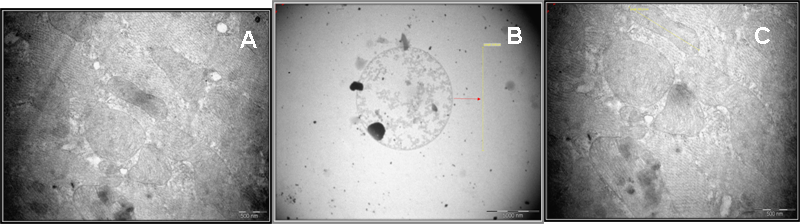

We next examined whether paraquat triggered mt ROS generation and cytochrome c release affects the mitochondrial morphology employing Transmission scanning electron microscopy. In unexposed control fishes, the morphology of the mitochondria did not change significantly (fig. 7A). However, fishes exposed to paraquat showed a striking disintegration of the mitochondrial morphology (fig. 7B).

To further assess whether FA-D reduces paraquat induced mitochondrial damage, fishes were exposed to 0.25 mg/kgBwt FA-D. FA-D fraction markedly prevented the decrease in complex-I activity induced by 55 mM paraquat (fig. 4). The same concentration was effective in normalizing the increment in mt ROS levels induced by paraquat (fig. 5). Exposure of fish to 0.25 mg/kgBwt FA-D effectively lowered the release of cytochrome c induced by paraquat (fig. 6, Trace B). At this particular concentration a strong absorption peak was observed at 560 nm indicating that the release of cytochrome c from mitochondria induced by paraquat administration was abolished. Furthermore, specific restoration of complex-I activity, cytochrome c release and mt ROS levels by FA-D effectively preserved the morphology of mitochondria following PQ induced neurotoxity in zebrafish (fig. 7C).

Fig. 7: Effect on morphology of mitochondria by TEM analysis A) Control B) PQ treated group C) PQ+FA-D treated group